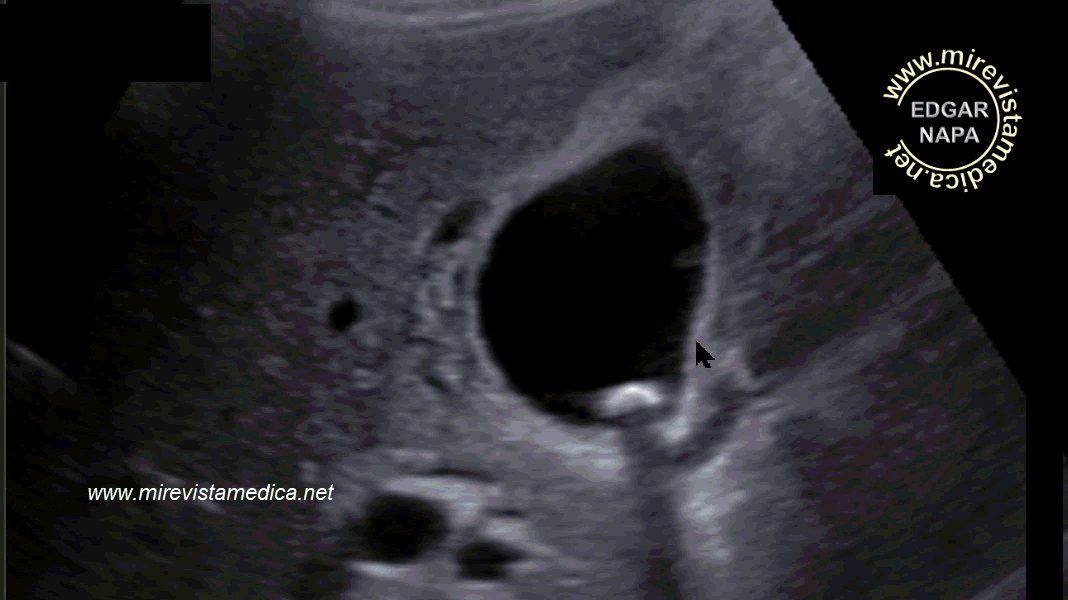

Semiología de los conductos intra y extrahepáticos en ultrasonido